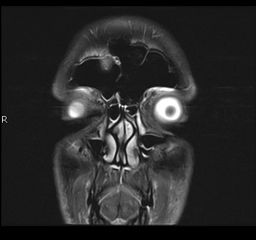

[Photo] L'IRM de mon cerveau

Les yeux tu veux dire ?

Ah c'est les yeux